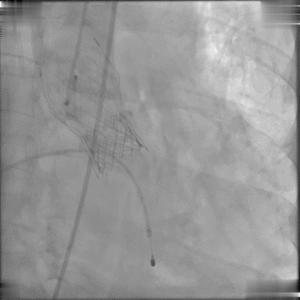

瓣膜定位释放

再行数十秒心脏按压,患者心脏恢复跳动、血流动力学状态恢复正常,即刻跨瓣压差为零,顺利结束手术。

即刻植入效果

当然,我们在如此紧急的情况下能够快速完成后续的一系列操作,与Sapien 3球扩瓣的优良设计密不可分。与传统的自膨瓣不同,该款瓣膜采用了独特的双调弯设计和低瓣架设计,即便是在复杂的冠脉解剖结构中,Sapien 3球扩瓣输送系统亦能非常轻松地过弓、跨瓣,并显著降低了输送过程中的血管损伤风险,这也是我们术中能够如此快速地将瓣膜精准送至植入部位的一大重要原因;在术后即刻影像学评估时,我们清晰地观察到,瓣膜植入位置非常精准,即刻跨瓣压差近乎为零;瓣架未对冠脉造成任何遮挡,患者血流动力学状态恢复良好;经过数天的术后监测,患者达到理想恢复状态,顺利出院返回澳门。